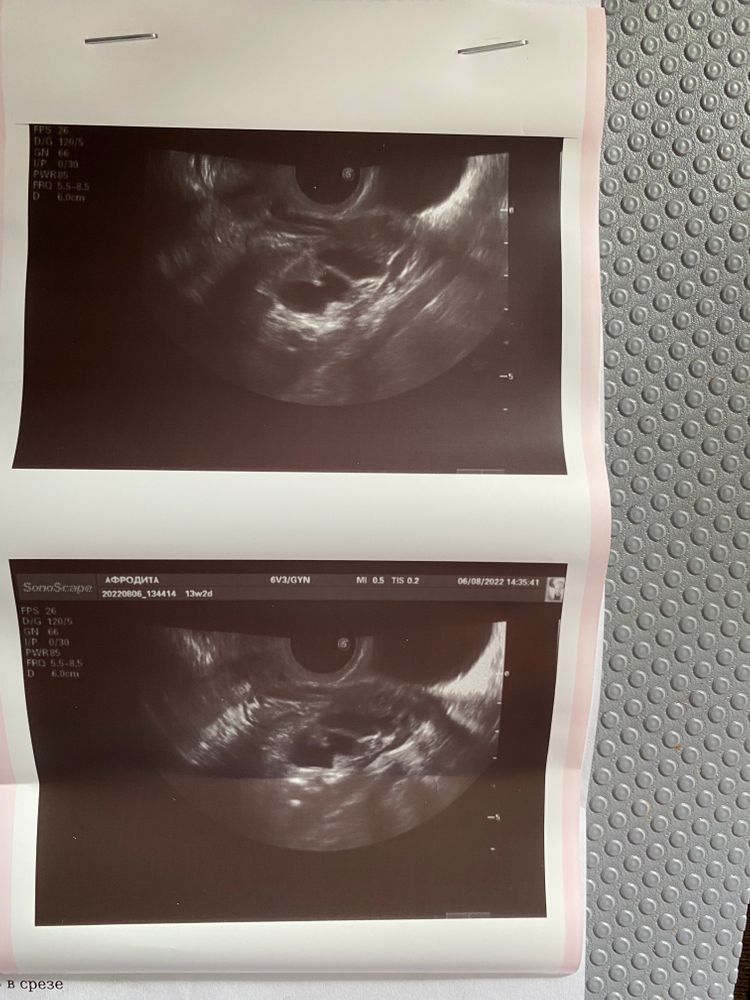

Добрый день! Сегодня была на узи и поставили такой диагноз, гидросальпинск. Начиталась уже всяких ужасов. До этого сколько делала узи, ничего подобного не было, делала проходимость 2 года назад,трубы проходимы. Что это все значит? До приема мне ещё далеко, так как жду всех ответов, так что с врачом не поговорить, азиат сегодня ничего не сказала. И ещё интересно, на 6 дц делала узи, фолликулы были хороших размеров, сегодня на 18 дц, они совсем крошки. Это как? Начала второй курс приема дюфастон. Это он так влияет? Дюфастон назначен с 15-24дц. Спасибо.

Это не ужасы. Когда вы делали тест на проходимость труб, 2 года назад, внутри образовались спайки, и где запаяно, там скапливается жидкость, выстилка трубы ее вырабатывает. И обычно, когда спаек нет, стекает в полость матки и через шейку матки - наружу, это самоочищение внутренних половых органов. Ее, этой слизи, обычно бывает совсем немного, обычно ее не замечают. Но тут она скопилась. Пройдет некоторое время и она постепенно рассосется. Ускорить этот процесс можно с помощью физиотерапии. Можно приобрести аппарат квантовой терапии "Витязь", он препятствует воспалительному процессу, рассасывает спайки, восстанавливает проходимость труб, доказано моей практикой. он вам поможет при травмах, при любых воспалениях. На втором месте грязелечение, и теперь не нужно никуда за этим ехать, продаются в готовых емкостях грязи Мертвого моря. Нужно делать грязевые "трусы" и вводить грязевой тампон вагинально. И смывать можно, когда грязь подсохнет и начнет стягивать кожу.